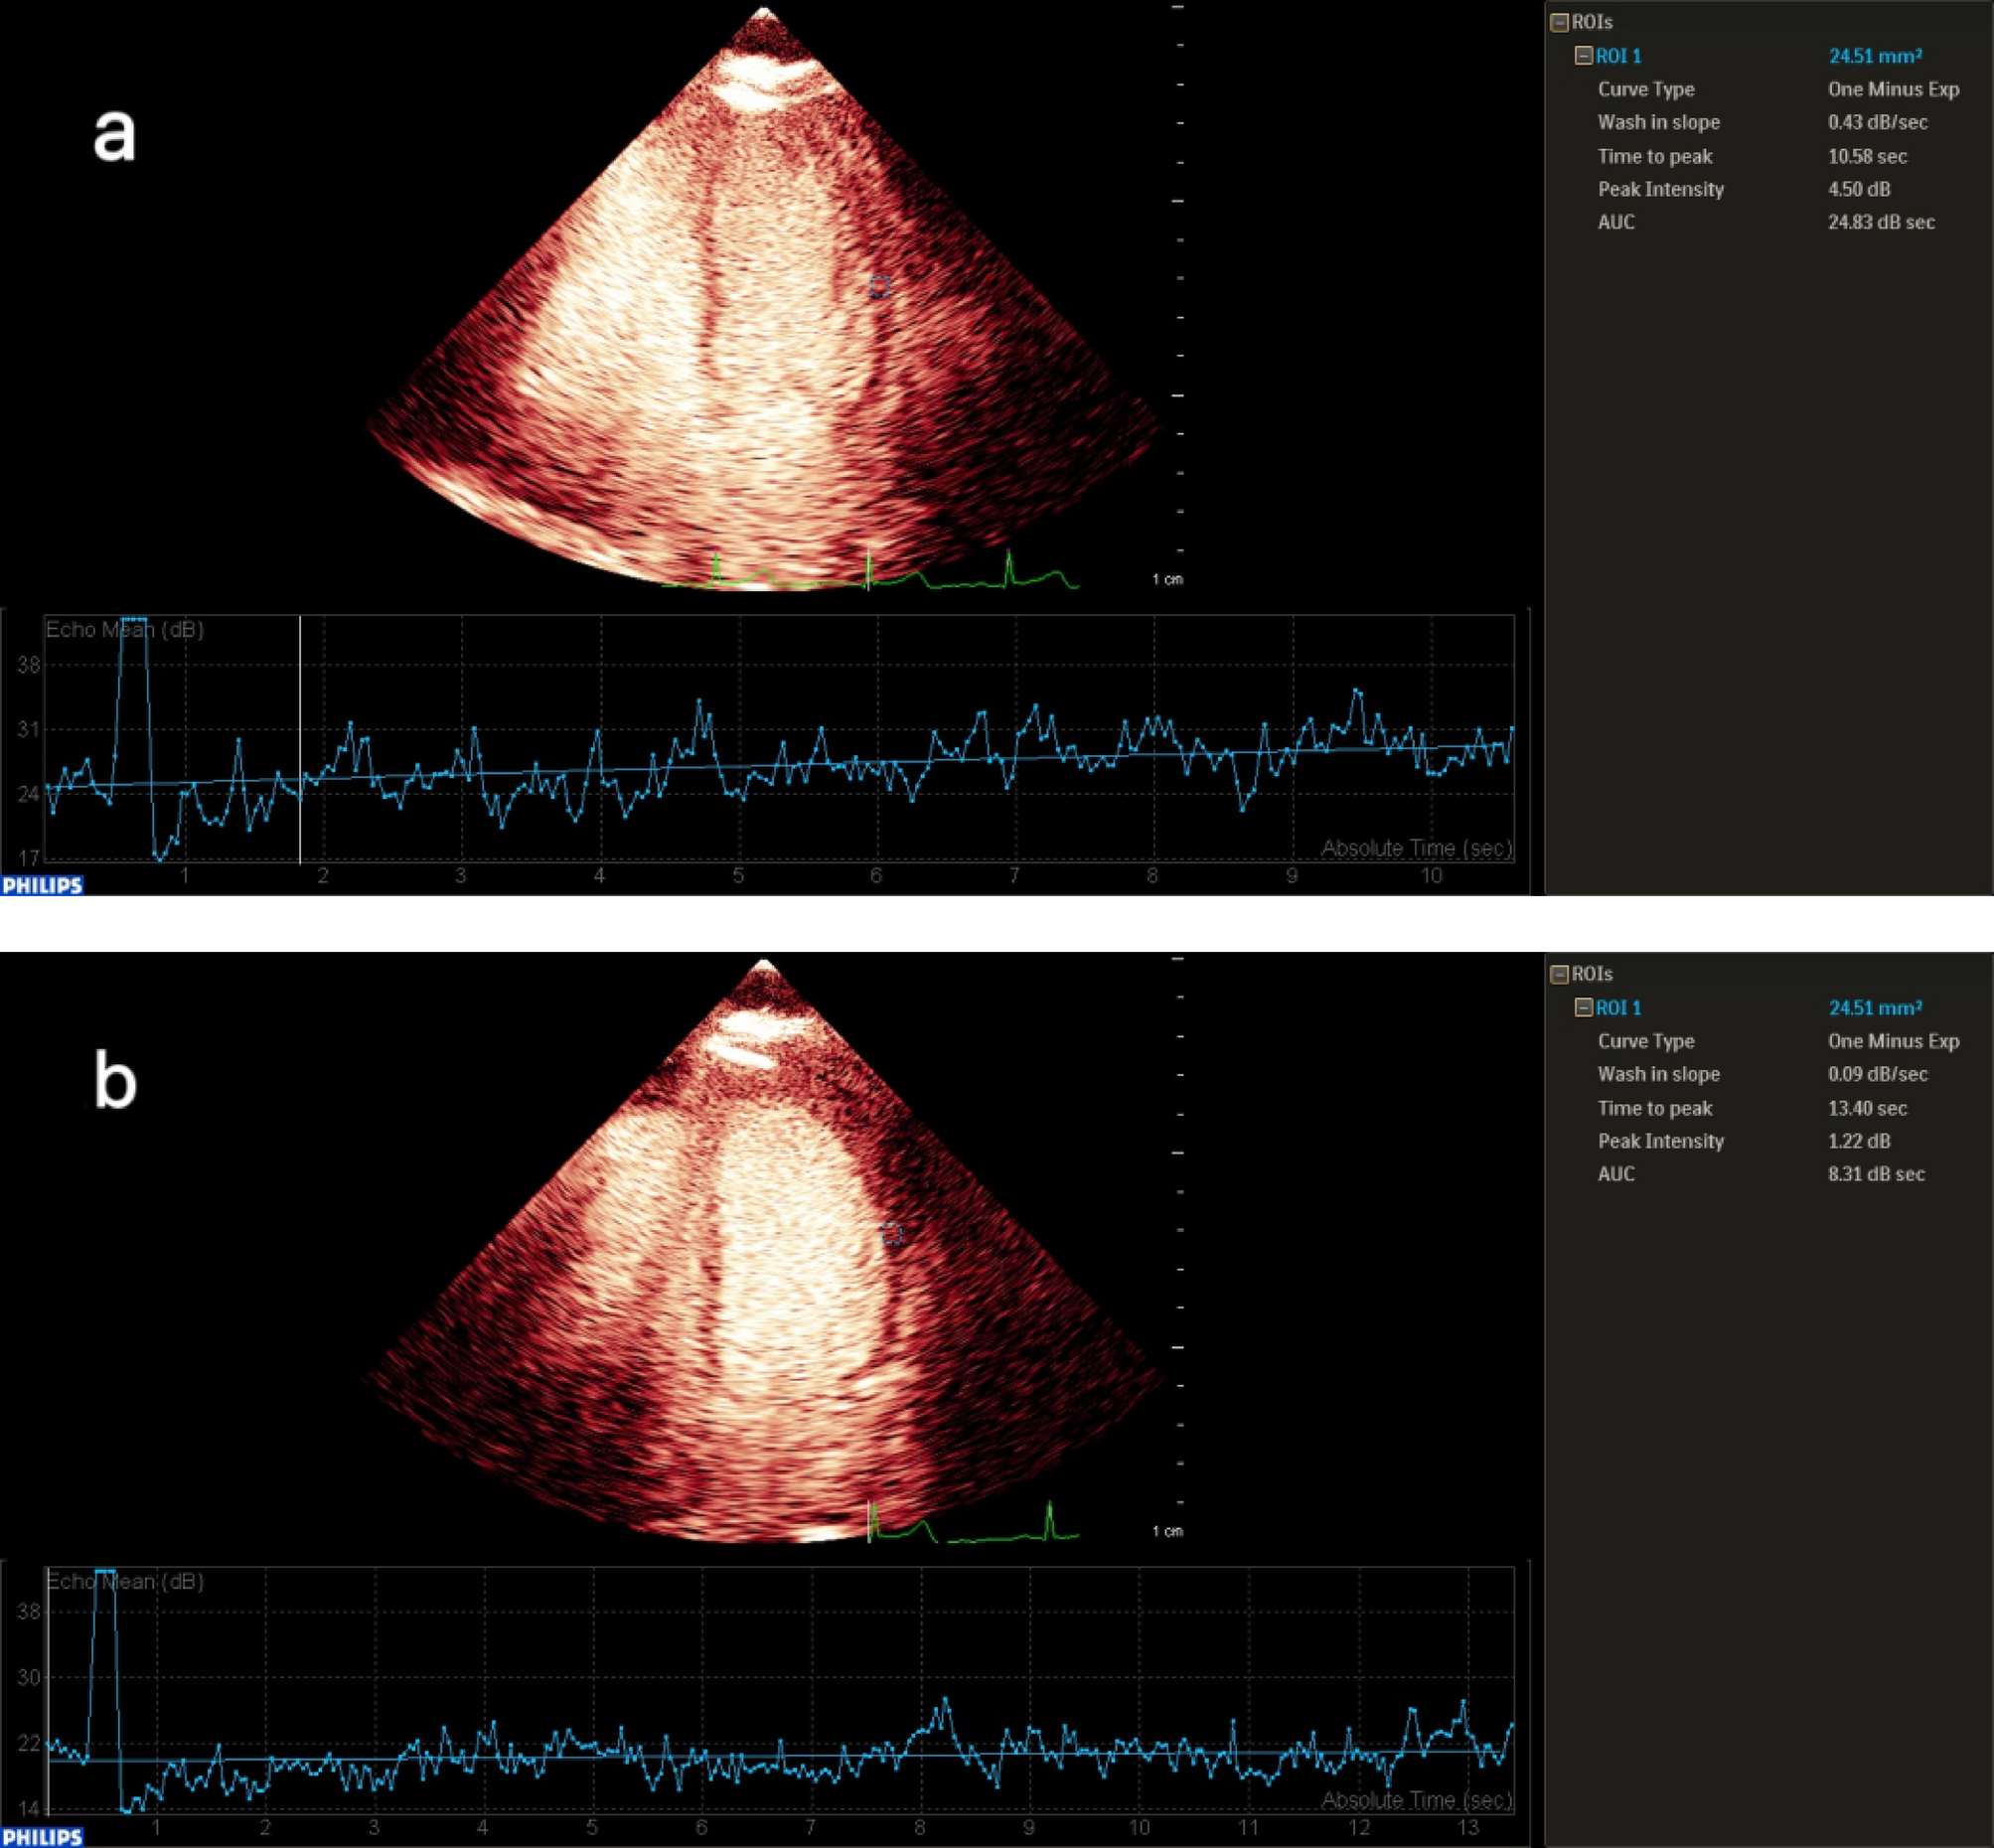

Quantitative analysis of contrast echocardiography of the left ventricular lateral wall in the INOCA group: After the drug load test (b), the contrast agent filling rate was significantly slower (Wash-in Slope 0.09 dB/s) compared to before the test (a), the time to peak was delayed (TTP 13.40 s), the peak intensity was reduced (Peak Intensity 1.27 dB), and the total contrast agent flow was significantly decreased (AUC 8.3 dB·s). This perfusion pattern (One Minus Exp curve) highly suggests that there is myocardial blood flow perfusion impairment in this area, and the possible cause may be microcirculation dysfunction. (a) Myocardial perfusion time-intensity curve of the left ventricular lateral wall in INOCA patients before drug stress test. (b) Myocardial perfusion time-intensity curve of the left ventricular lateral wall in INOCA patients after drug stress test.